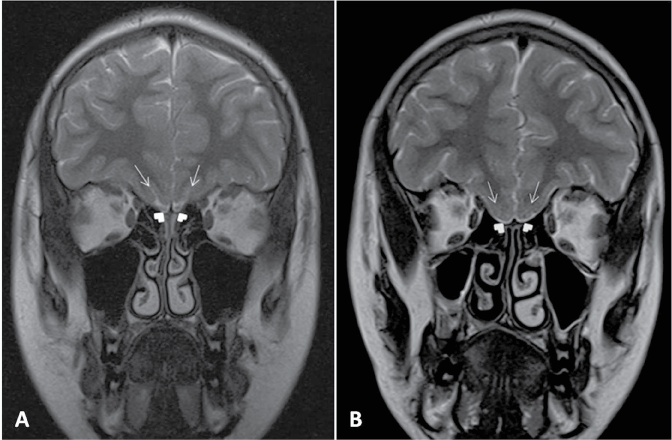

A 14-years-old male was consulted for cryptorchidism and anosmia. There was decrease of LH, FSH and testosterone in the laboratory examinations of the patient. We used Magnetic Resonance Imaging (MRI) to visualize the olfactory tract and evaluate the olfactory sulci in patient whose clinical and laboratory findings were compatible with Kallmann syndrome. Coronal images of the frontal region clearly demonstrated aplasia of the bilateral olfactory sulci and absence of the olfactory tracts in the patient (Figure 1).

Figure 1: Coronal T2 weighted images. A) Normal MRI finding of bilateral olfactory sulcus (arrows) and olfactory bulbs (arrowheads); B) In the patient with Kallmann syndrome, bilateral olfactory sulcus (arrows) and olfactory bulbus cannot be seen (arrow heads).